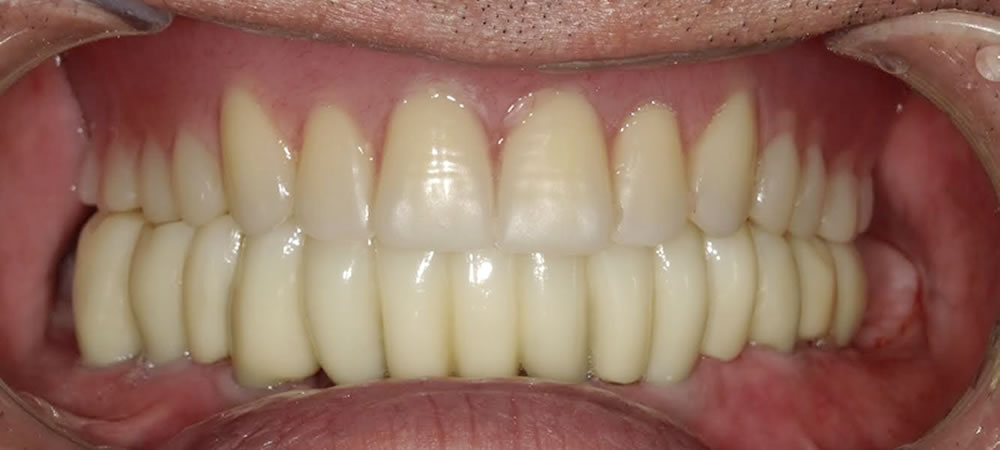

埋入後はフィクスチャーと、骨がオステオインテグレーションするのを待ち、しっかりとくっついている事を確認し、上部に歯を作成していきました。

治療完了

噛み合わせや歯並び、歯の長さを測り、審美的に綺麗になるように作成する事ができました。結果、見た目の改善、咬合の改善をする事ができ、しっかりと食事をする事ができるようになりました。